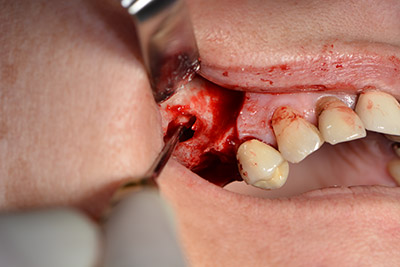

Хирургична процедура за имплантиране

Класическият разрез (крестално, букално освобождаване) и подготовката на мукопериостално ламбо осигуряват добра видимост.

Фенестрацията е извършена при 35,000 rpm и след това носната лигавица е обработена по посока на челюстта (Фиг. 13 to 14).